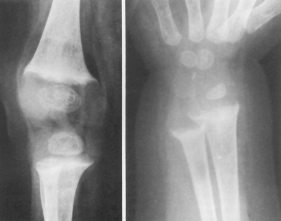

GONARTROZA se întâlneste mai frecvent la femei, dupa menopauza. Este secundara când apare dupa leziuni preexistente: genum valgum, varum, luxatie congenitala de sold, traumatisme ale genunchiului.

Radiologic: reducerea spatiului articular si osteofite. Ele se evidentiaza pe radiografia de profil. La nivelul articulatiei femuro-tibiale se evidentiaza pensarea inegala a articulatiei, derotunjirea suprafetelor articulare, largirea si alungirea spinelor tibiale prin osteofite, scleroza suprafetelor articulare, aparitia de formatiuni pseudochistice în platourile tibiale, osteofite.